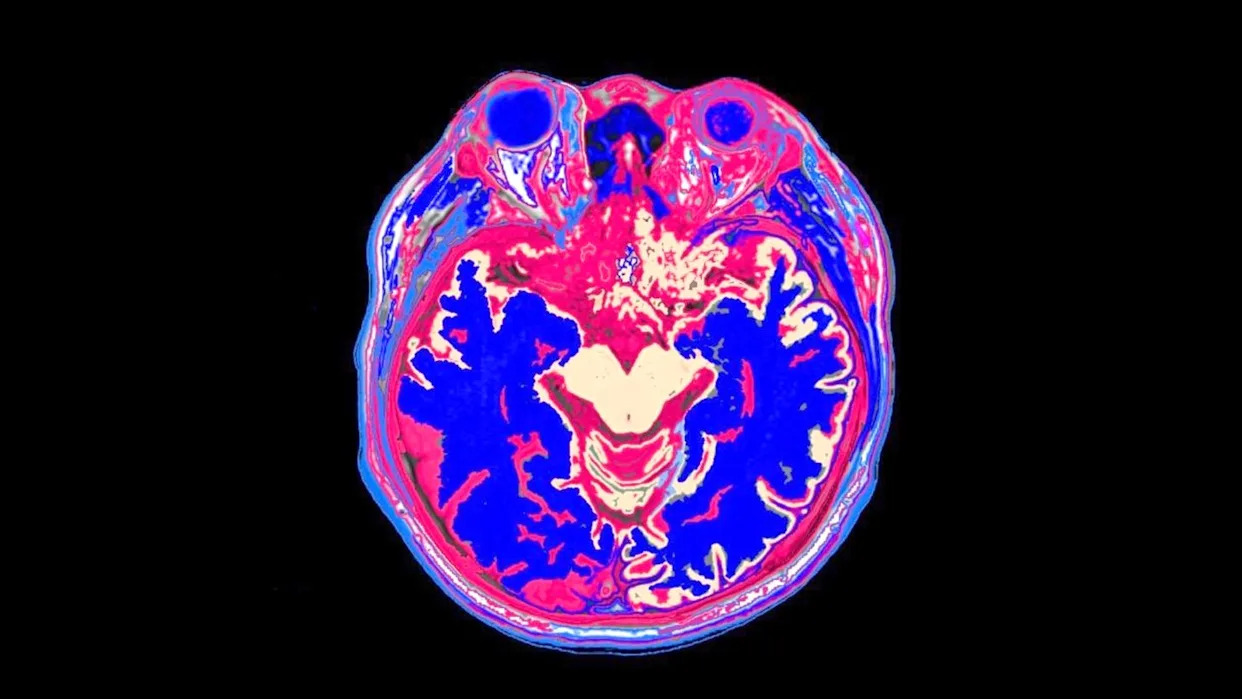

پس از یک هفته، سلولهای بنیادی عصبی انسان به نواحی آسیبدیده مغز موشها که از نظر ژنتیکی مهندسی شده بودند تا بدنشان سلولهای انسانی را بپذیرد، پیوند زده شد. سکته مغزی منجر به کاهش شدید جریان خون، مرگ برخی بافتها و اختلال حرکتی شده بود. با این حال، بلافاصله پس از درمان، ضایعات کمی کاهش یافت. سپس پیشرفت سلولهای پیوند شده از طریق تصویربرداری زیستتابی بررسی شد و دو هفته زمان برد تا سیگنالهای درخشش شروع به تشدید کنند. این اتفاق به محققان نشان داد که مغز آسیبدیدهای که به تازگی دچار سکته مغزی شده است، پیش از درمان به زمان برای تثبیت وضعیت نیاز دارد.